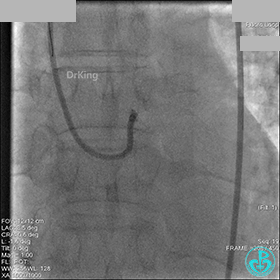

AL 1.0指引导管到位,简单短时尝试导丝不能顺利通过前降支或回旋支病变。改变策略处理右冠脉病变,计划植入2枚支架。AL指引导管到位,Sion blue导丝到达右冠脉远端。导丝通过后1.5mm及2.5mm球囊14~16atm充分扩张中段病变。

右冠脉中段充分扩张后欲植入3.5×38mm支架时,支架难以通过中远段扭曲处,且指引导管、导丝弹出飞扬。反复尝试导丝重新到达右冠脉远端时通过不顺利,局部造影剂滞留,远端血流接近3级。

右冠脉血流3级,患者无症状,终止手术。